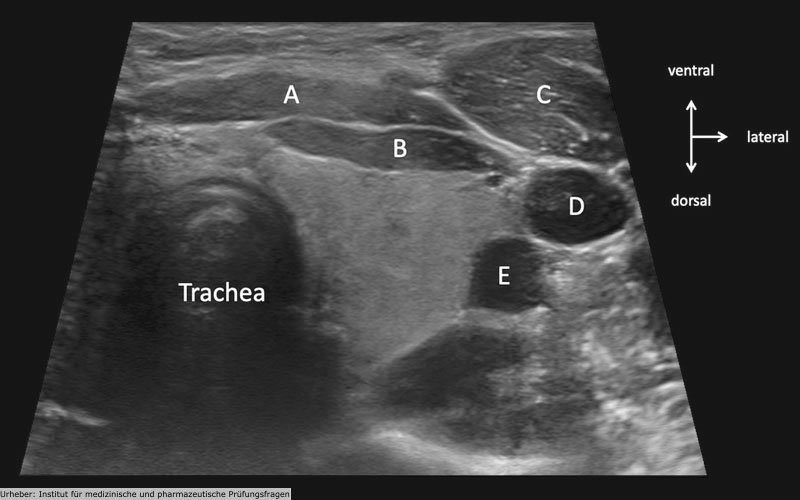

2.87 Die Abbildung zeigt eine sonografische Darstellung des Halses. Die Orientierung (ventral, dorsal, lateral) ist im Piktogramm oben rechts angegeben. Welcher Buchstabe in der Abbildung bezeichnet die Vena jugularis interna?

Antwortmöglichkeiten

- (A) A

- (B) B

- (C) C

- (D) D

- (E) E